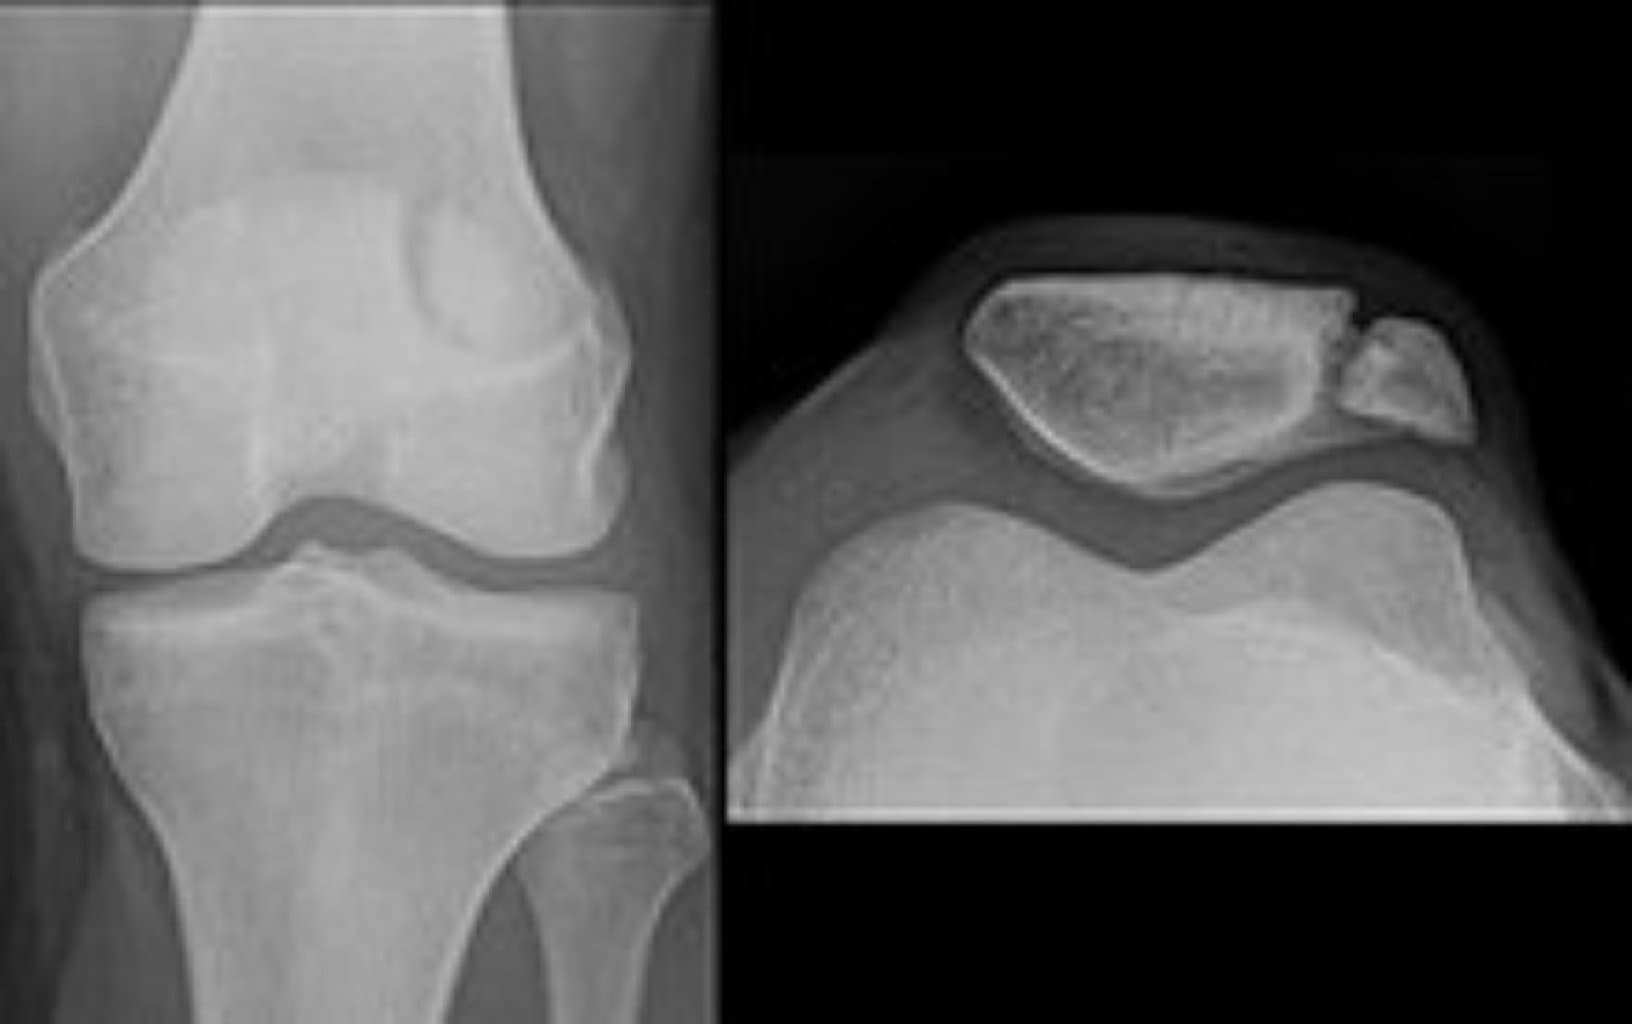

Diaqnoz

Diaqnoz adətən fiziki müayinə və radioloji testlər (məsələn, röntgen, CT skanı) ilə qoyulur. Bu testlər, sınığın yerini, növünü və şiddətini müəyyənləşdirmək üçün vacibdir.